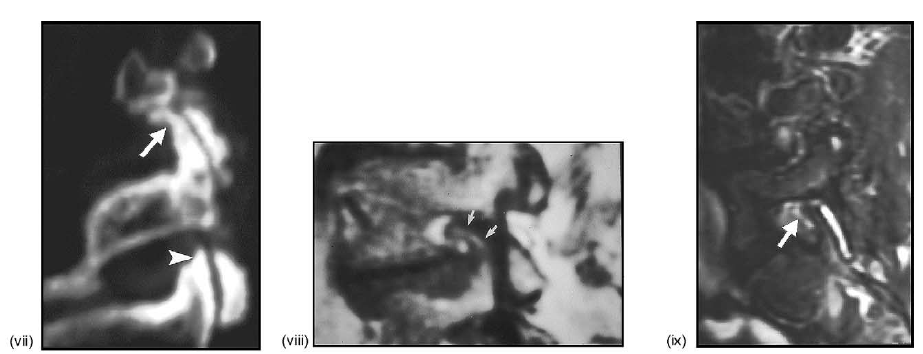

sagittal plane of subjacent vertebra. (H) Medical imaging studies: (i) midline sagittal T1-weighted MRI showing a grade I anterolisthesis of L4 on L5

(arrow: compare with (A)). (ii) Parasagittal T1-weighted MRI showing the anterolisthesis of L4 (arrow) on L5, the anterior angular bending/remodeling

of the superior articular process of L4 (asterisk), and the stenosis of the inferior recess (black arrowhead) and relative patency of the superior recess

(white arrowhead) of the L4-L5 spinal neural foramen; same case as in (i) (compare with (B)). (iii) Midline sagittal T1-weighted MRI showing grade

I anterolisthesis of L5 (arrow) on S1. (iv) Axial T1-weighted MRI at L5-S1 showing the near sagittal orientation of the angulation of the posterior

spinal facet joints (arrows) in the axial plane on both sides; note the stenosis of the central spinal canal (dot) and the spinal neural foramina bilaterally

the displacement of the spinous process (dot) toward the right side as a result of the rotoscoliosis (compare with (G)). (vii) Parasagittal T2-weighted,

fat-suppressed MRI showing Type I hyperintense edematous vertebral marrow alterations involving the pedicles, pars interarticulari, and articular facet

processes at the L4 and L5 levels (arrows; compare with (B)). (viii) Parasagittal T1-weighted MRI showing Type II hyperintense fatty marrow alteration

within the pedicle (arrows) and inferior articular facet process (arrowhead) of L5; note the complete obliteration (i.e., stenosis) of the neural foramen at

L4-L5 (dot) (compare with (C)). (ix) Parasagittal T1-weighted MRI showing the Type III hypointense sclerotic alteration of the vertebral marrow within

the posterior bony structures at multiple spinal levels inferiorly (asterisks; compare with (D)).